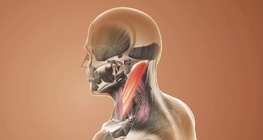

Anatomy of the trunk and neck muscles.